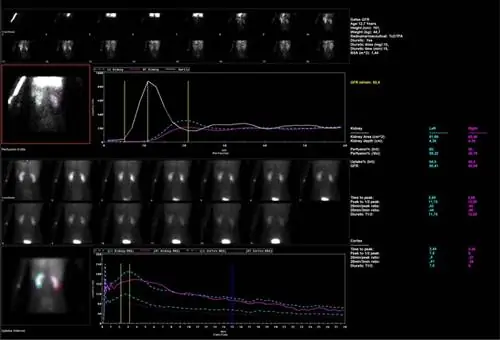

Динамическое исследование почек представляет собой серию изображений, записанных в течение приблизительно 25-30 минут в положении пациента на спине. Полученные изображения позволяют количественно и качественно оценить функцию почек, скорость экскреции с мочой, скорость клубочковой фильтрации и другие параметры их функции. Этот тест применим к пациентам с подозрением на нефрогенную гипертензию, но дополнительно необходимо провести тест после введения каптоприла - препарата, который также используется для лечения гипертензии. Еще одним преимуществом динамического исследования почек является возможность оценки нарушений оттока мочи из чашечно-лоханочной системы, часто возникающих при течении нефролитиаза у взрослых или врожденных пороков развития у детей. Эти тесты очень полезны и безопасны даже для очень маленьких детей: их можно повторять через определенные промежутки времени, чтобы лучше отслеживать последствия лечения, например хирургического вмешательства. Тест дает цифры, которые позволяют сравнивать функцию каждой почки с течением времени.

Динамические почки, диабет 1 типа